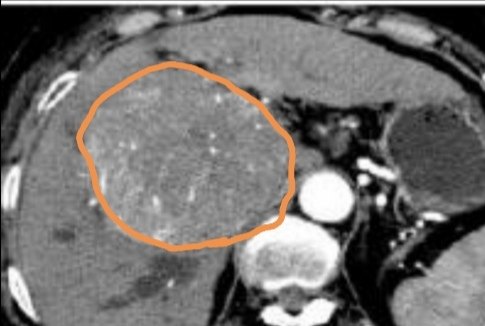

腹部超声检查的是腹腔内肝胆胰脾肾的形态大小。慢性肝病的患者需要定期复查,大夫要求三个月复查一次?嗯?会不会太勤?答案是:不会啊!因为,有慢性肝病的患者(乙肝,丙肝,酒精肝,长期肥胖导致的脂肪肝,慢性药物性肝损伤,自身免疫系肝炎,原发胆汁性胆管炎,胆管结石继发於胆型胆管炎……等等,很多种原因造成肝脏慢性损伤过程),尤其有家族史的患者,罹患肝脏肿瘤(肝细胞癌,胆管细胞癌)的风险比正常健康人高出很多倍!而三个月的时间对于肿瘤发生,一般还来得及处理,外科手术或局部介入治疗都来得及。很多肿瘤治疗及时,都是可以不影响生活质量和生存期的。所以,及时并按时复查对于所有慢性病患者来说,都很重要狠重要的!

1、慢性肝病3个月左右筛查超声,主要排查肿瘤;